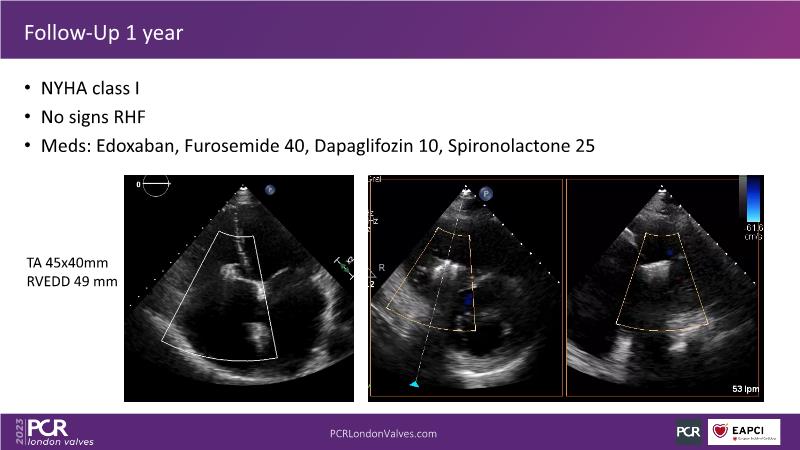

This session offers an opportunity to engage in a real case discussion led by an advanced Heart Team. Participate in discussions on controversial decision-making scenarios and stay informed about the latest clinical evidence related to MitraClip, Tendyne, and TriClip therapies.